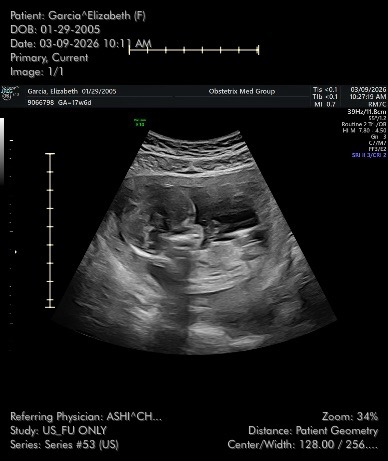

Nothing could ever prepare a parent for this kind of pain. We had so many hopes and dreams for our baby boy, and now we are left grieving a loss that words can’t fully express. Beginning my second trimester, we were informed of potential complications regarding our son’s size compared to his gestational age and were referred to a maternal fetal medicine specialist. Learning of such heavy news caused immense worry and destress within us and our families.